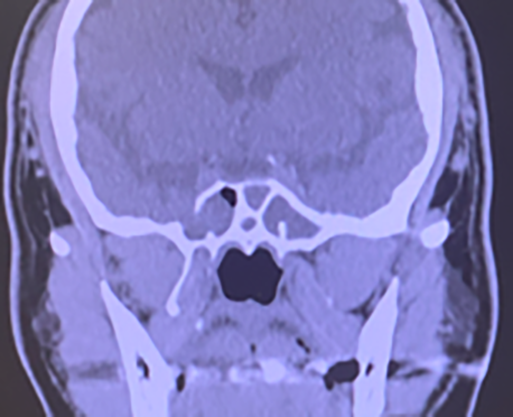

左副鼻腔真菌症(Coronal CT)

左篩骨洞に不均一な陰影が存在、石灰化も認める。患側の骨肥厚を認めるが、骨破壊はない。